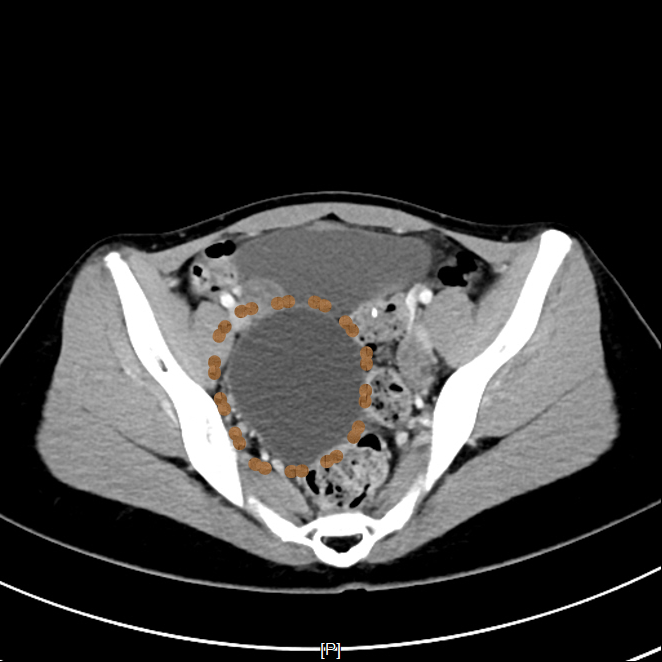

▲患者CT影像

超声介入张轶亮主治医师了解老赵的病情后立刻为其超声检查,发现右肾囊肿确实很大,已经压迫了周围肾组织。

考虑到老赵年事已高,行动不便,王晓明副主任医师当即电话联系泌尿外科,安排其住院,并行CTU(尿路造影)、血凝等术前常规检查,第二日在局部浸润麻醉下进行超声引导下肾囊肿穿刺抽液硬化治疗。

一个月后,老赵复查发现右肾囊肿已经缩小到1cm以内,体积缩小率高达99%老赵表示非常满意。